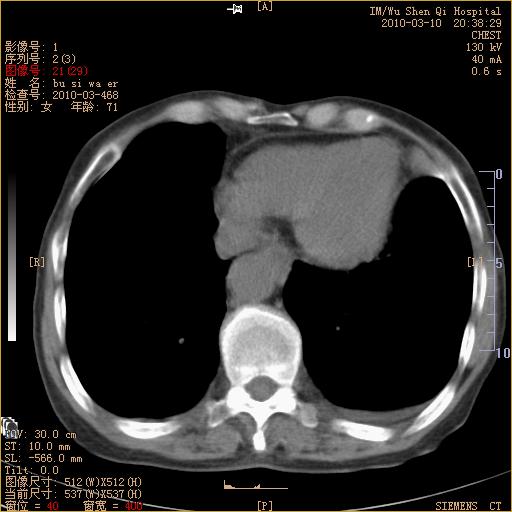

以下是引用随光逐影在2010-3-11 0:41:00的发言:[br]1)考虑左肺及右肺上叶继发性肺结核并左肺炎症感染。2)左侧支气管内膜结核可能;建议必要时行纤支镜检查。3)肺气肿。4)心包膜增厚(或少量心包积液)。5)左侧胸腔积液。